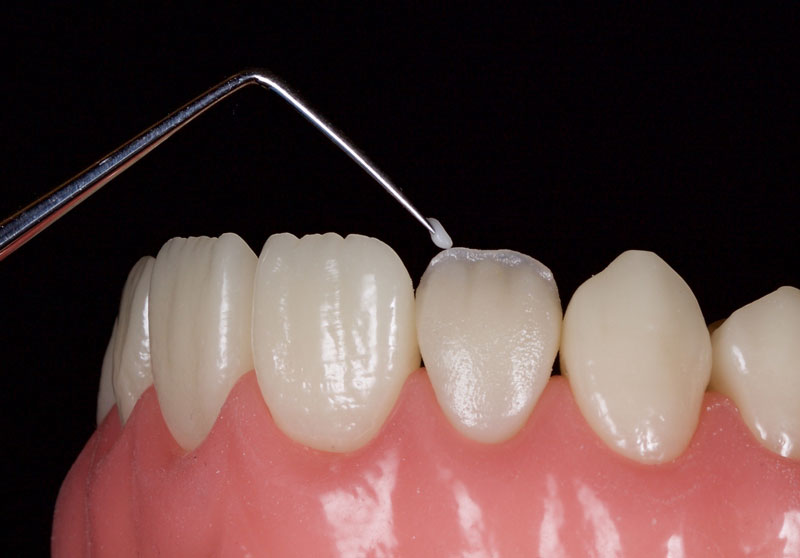

Finally, the incisal third is overlaid facially with a highly translucent enamel shade, e.g., WE Tokuyama (Fig. 14). This is smoothed and adapted with a No. 3 artist’s brush and a wetting resin.